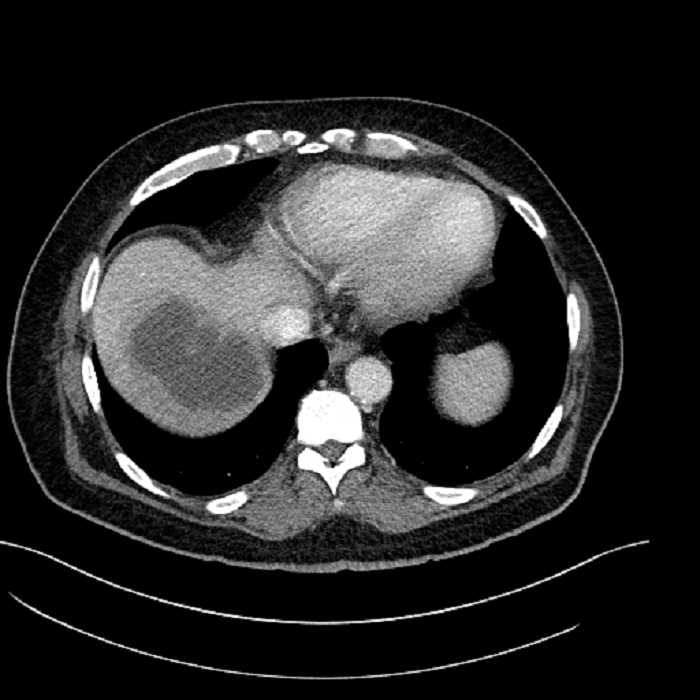

• Large fluid density structure in hepatic segments 7 and 8 measuring 10 x 7 x 7 cm with internal septation and circumferential ill-defined low density compatible with edema

• Peripherally enhancing subcapsular collections along the anterior margin of the left hepatic lobe measuring 3 x 1 cm and 2 x 1 cm

Acute sigmoid diverticulitis complicated by a small contained perforation and a large abscess in the right hepatic lobe. Additional small subcapsular abscesses along the anterior margin of the left hepatic lobe.

• The classic CT imaging appearance is a double target sign with internal low density surrounded by an internal enhancing rim (capsule) and a low density external rim (edema)

Hepatic abscess showing the double target sign with low density internally surrounded by a thin inner enhancing rim (red arrow) and ill-defined outer low density rim (yellow arrow). Blue arrow indicates an internal septation. Red arrows: additional smaller subcapsular abscesses. Red arrow: focal contained perforation associated with diverticulitis.